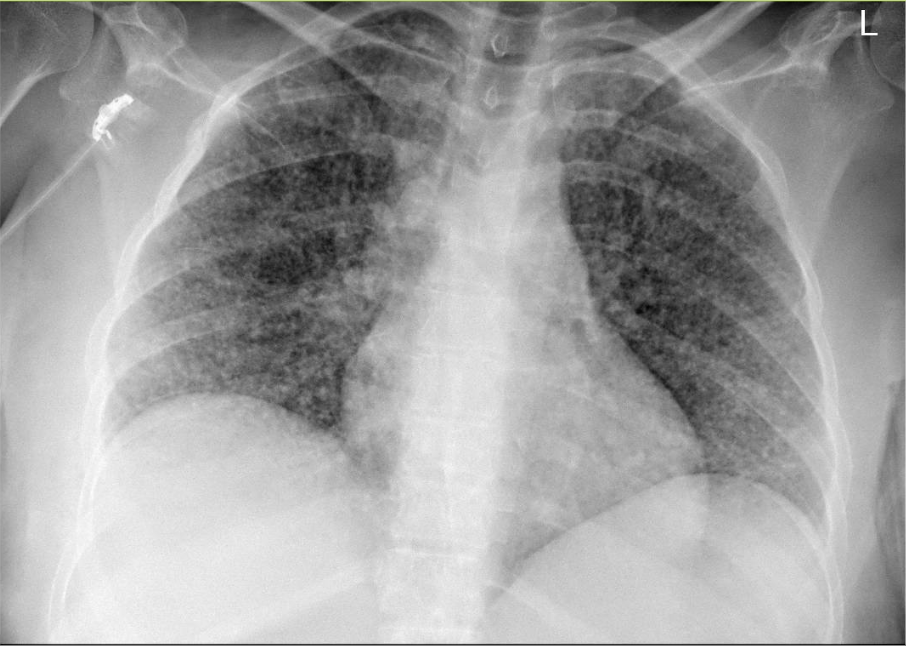

Gepubliceerd: Week 49 - 2024 2262 deelnemers Een zwangere vrouw uit India heeft sinds enkele weken een droge hoest en nu ook koorts en hoofdpijn. De voorgeschiedenis is blanco. Ze wordt plotseling verward. Wat is de diagnose? Antwoord pulmonale metastasen tuberculose sarcoïdose pneumoconiose Antwoord controleren